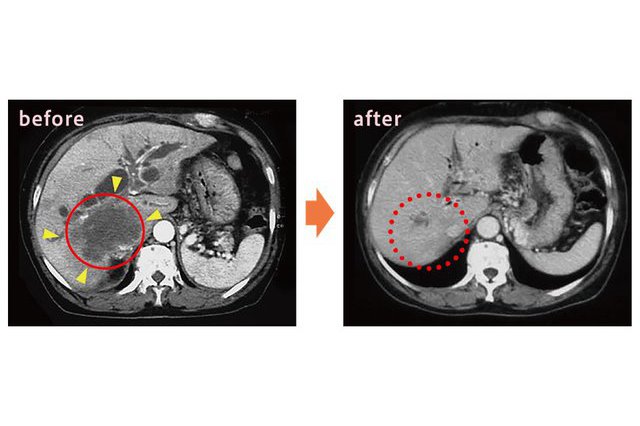

アルツハイマー型認知症を「治す・改善する」ことは難しくても、早い段階で診断できれば「進行をゆるやかにする」ことはできます。 2023年に新たに国内で保険承認されたアルツハイマー型認知症の点滴治療薬「レカ...